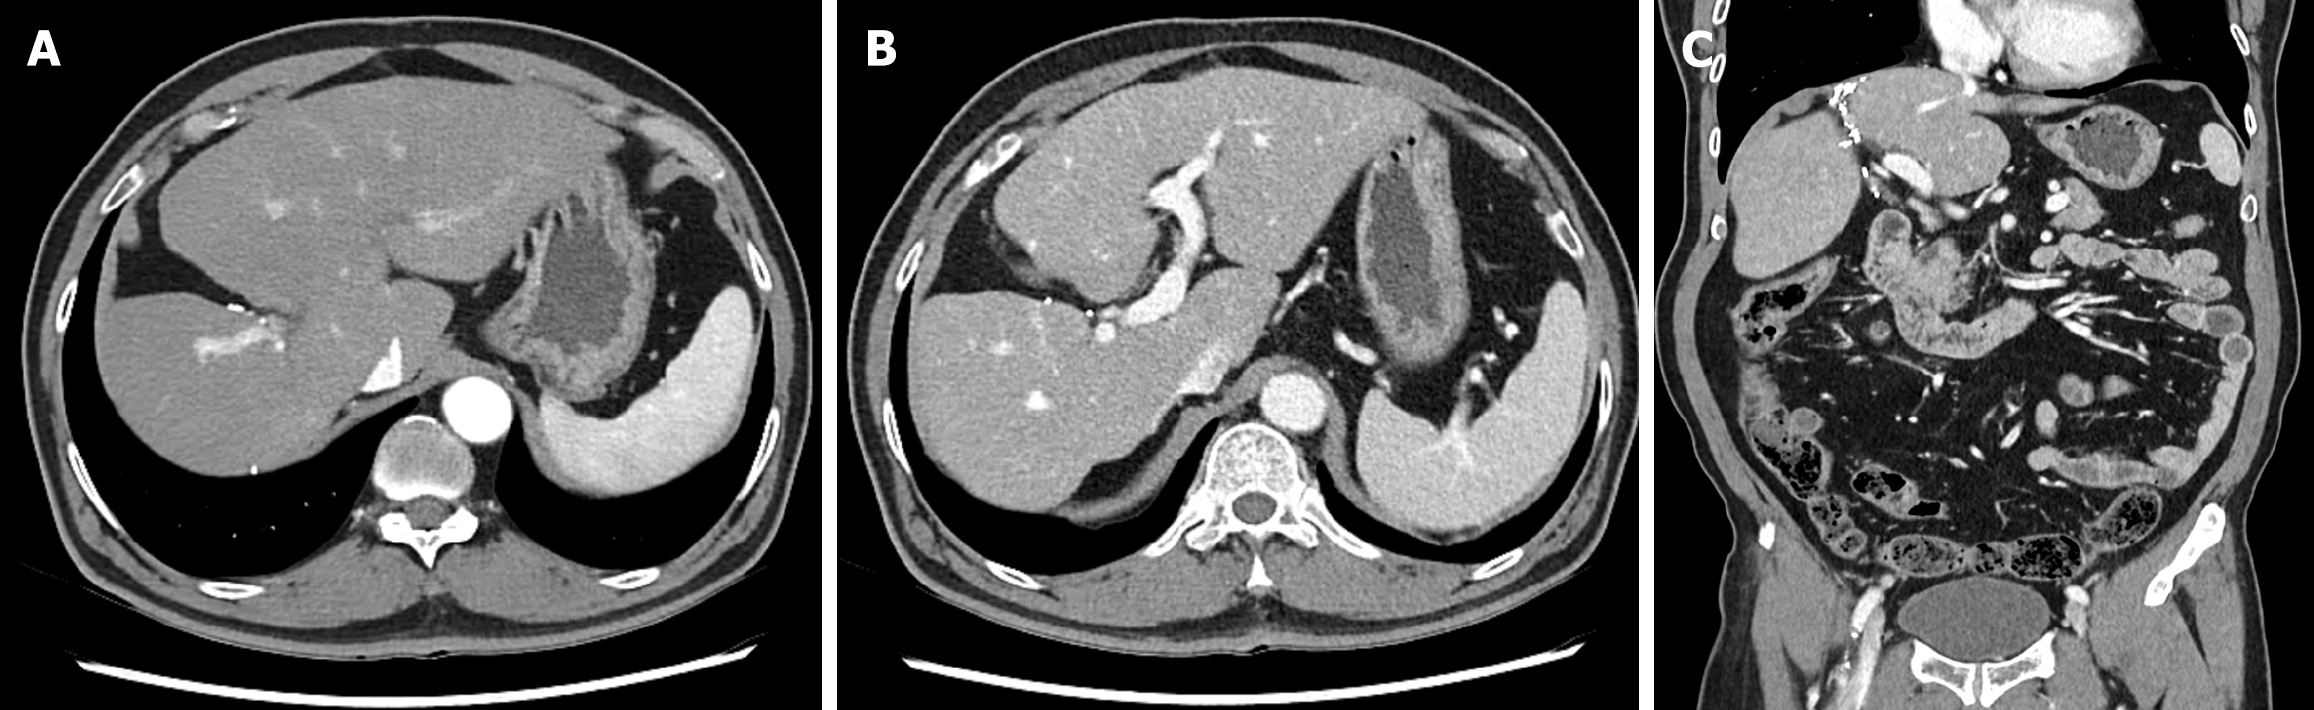

Abdominal contrast-enhanced CT and MRI demonstrated a 3 cm centripetal enhancing lesion located in the right hepatic dome, raising the suspicion of a malignant lesion such as cholangiocarcinoma or recurrent RCC metastasis. The lesion exhibited ill-defined margins without any evidence of major vessel invasion or distant metastasis (Figure 1).

Based on imaging findings, a 3 cm liver mass was identified in segment 8 (Figures 1 and 2), with no evidence of distant metastasis to the abdomen or chest. Based on these findings, a radical resection was performed. Considering the advantages of minimally invasive surgery, a laparoscopic right anterior sectionectomy was performed.